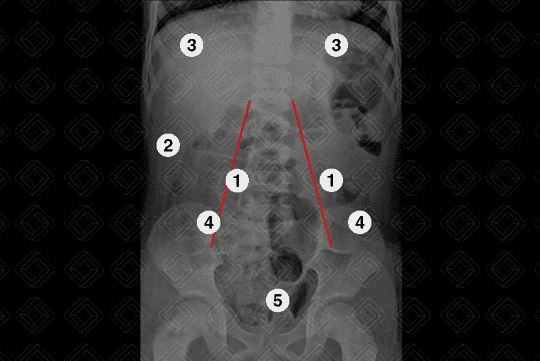

Descrição da figura 1: Radiografia de abdome normal em decúbito dorsal evidencia a distribuição normal dos gases intestinais. (1) Projeção do músculo psoas bilateralmente; (2) gordura pré-peritoneal normal; (3) hemicúpulas diafragmáticas; (4) cristas ilíacas; (5) reto.

Texto alternativo para a imagem Figura 4. Créditos: Dra. Elazir Mota - Rio de Janeiro/RJ

Descrição da figura 4: Presença de volumoso fecaloma no reto e sigmoide (setas vermelhas); paciente com relato de importante constipação desde o nascimento, sem melhora clínica. Para mais informações, acesse Constipação Funcional.